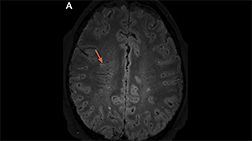

Axial FLAIR MRI from a patient with AQP4+ NMOSD demonstrating an "arch bridge" lesion in the splenium of the corpus callosum (arrow; Image courtesy of Dr. Carlos Sollero).